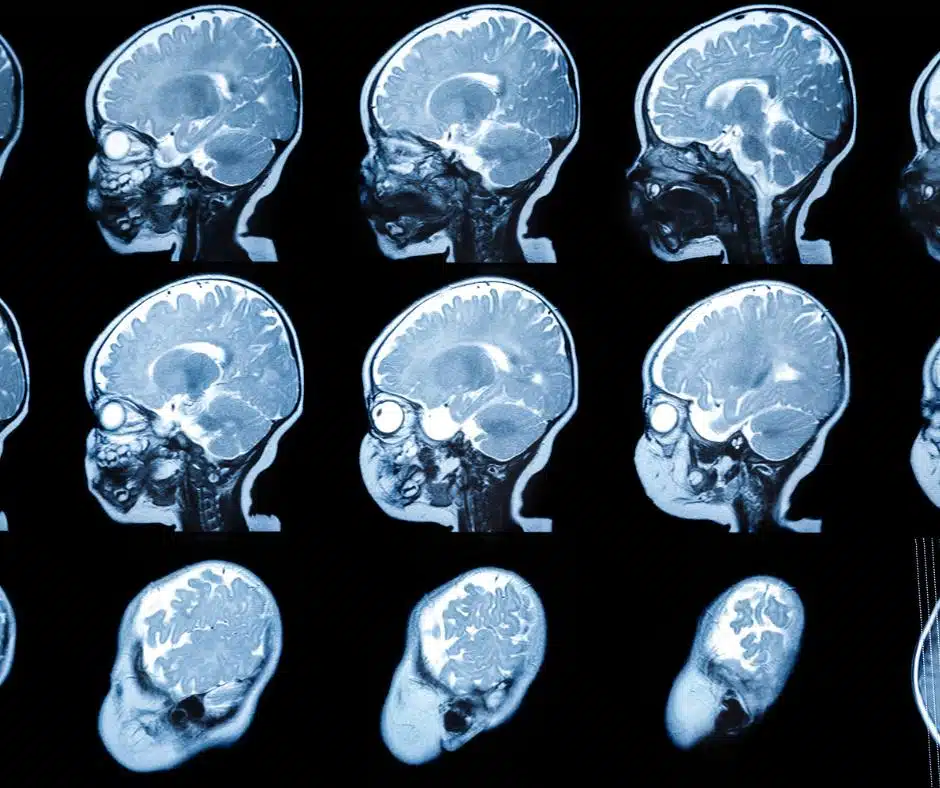

แพทย์จะวินิจฉัยโรค MLD จากประวัติอาการ การตรวจร่างกาย การตรวจทางระบบประสาท การตรวจเลือดเพื่อวัดระดับเอนไซม์ ARSA การตรวจปัสสาวะเพื่อหาระดับซัลเฟไทด์ที่สูงผิดปกติ การตรวจคลื่นไฟฟ้าสมอง (EEG) การตรวจคลื่นแม่เหล็กไฟฟ้าสมอง (MRI) และการตรวจทางพันธุกรรมเพื่อยืนยันการกลายพันธุ์ของยีน ARSA หรือ PSAP